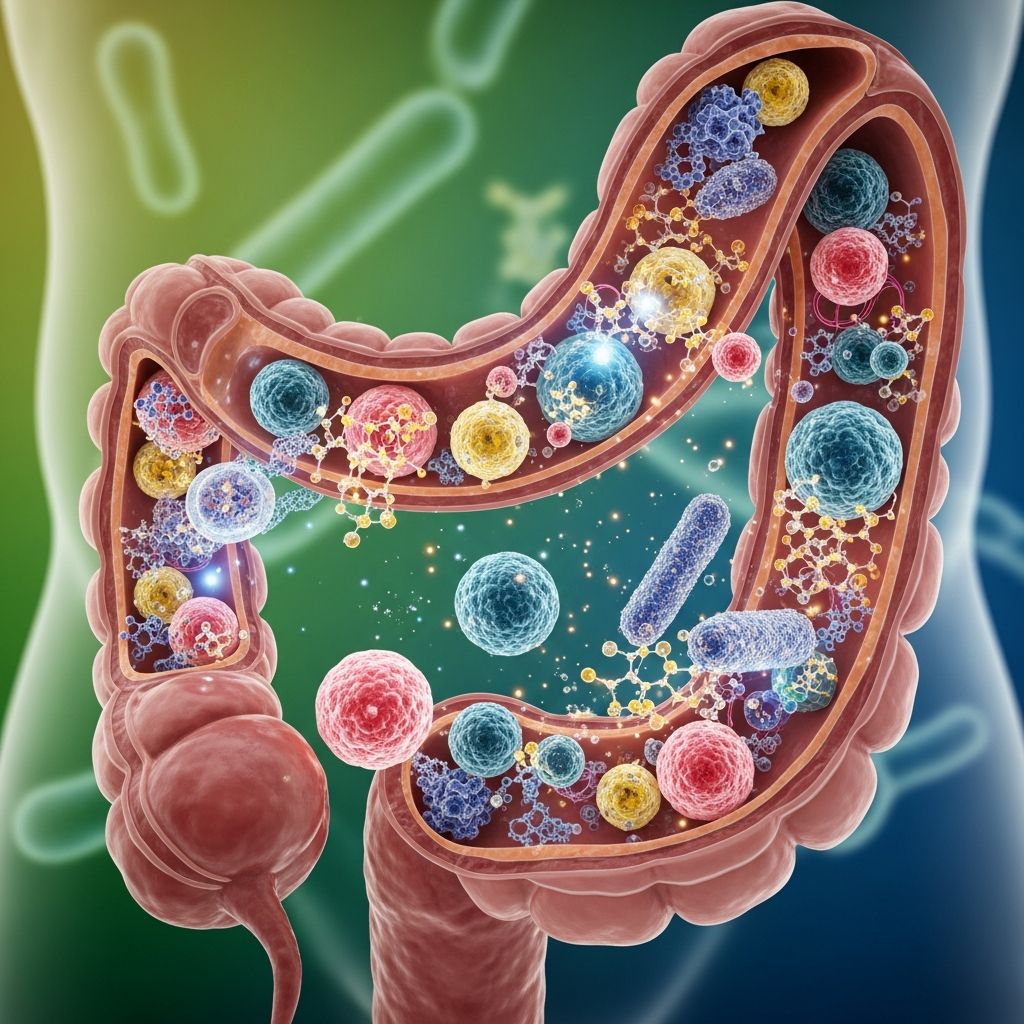

The human gut microbiome has become one of the most studied and discussed aspects of modern nutrition science. Within this complex ecosystem of trillions of microorganisms, prebiotics play a crucial yet often misunderstood role. Unlike probiotics, which are living microorganisms themselves, prebiotics are non-digestible food components that act as fuel for the beneficial bacteria already present in your digestive system. Understanding prebiotics and their function is essential for anyone interested in optimizing their gut health through nutrition.

Prebiotics consist of non-digestible fermentable carbohydrates that serve as food sources for probiotics and other beneficial microorganisms in the colon. These specialized compounds pass through the upper digestive tract largely unchanged, resisting digestion by human enzymes until they reach the colon, where they become fuel for beneficial bacteria.

The fermentation process is key to understanding how prebiotics work. When beneficial bacteria ferment prebiotics, they break down these compounds and produce metabolic byproducts that have significant health implications for the host.

- Increase beneficial bacteria: The fermentation of prebiotics by gut bacteria helps increase the amount of beneficial bacteria strains in the colon, promoting a more diverse and robust microbial ecosystem.

- Prevent pathogenic growth: By feeding beneficial bacteria preferentially, prebiotics help prevent the growth of potential pathogens that could compromise digestive health.

One of the most important outcomes of prebiotic fermentation is the production of short-chain fatty acids (SCFAs), particularly butyrate, propionate, and acetate. These compounds are not merely waste products but rather beneficial metabolites with significant health properties. SCFAs serve as energy sources for colonic cells, regulate pH in the intestines, and provide anti-inflammatory benefits throughout the digestive tract.

Research has demonstrated that certain bacteria, particularly butyrate producers, play essential roles in maintaining gut barrier function and reducing metabolic inflammation. The presence of adequate butyrate-producing bacteria has been associated with improved insulin sensitivity and better metabolic health overall.